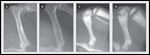

FIGURE 3

Radiographic Signs of Osteopenia and Osteopetrosis in Mice

Several members of the tumor necrosis factor (TNF) superfamily of proteins- RANK, RANK ligand, and OPG-are key to enabling osteoclasts to resorb bone and maintain balanced bone remodeling. The importance of RANK ligand has been studied in experimental systems, in which knockout mice lack RANK ligand or the RANK gene; these mice have no osteoclasts and develop osteopetrosis (Figure 3).[5, 6] The interaction between the RANK receptor on osteoclast precursors and the RANK ligand expressed by immature osteoblasts and bone marrow stromal cells is critical for osteoclasts to form, function, and survive.[6] RANK ligand binds to the RANK receptor on osteoclast precursors, promoting their differentiation into mature osteoclasts capable of osteoclastic activity.